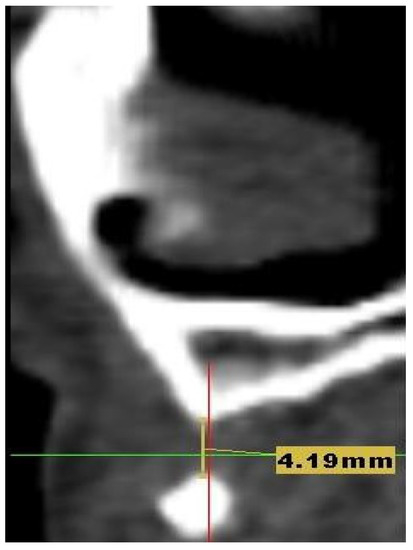

2. Case Presentation